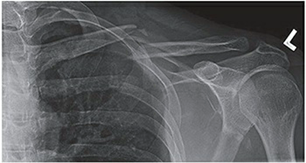

Radiographic Evaluation and Templating

Standard radiographic evaluation includes an anteroposterior (AP) view of the clavicle and a 15 to 20 degree cephalic tilt view. The cephalic tilt view projects the clavicle free from the underlying ribs and provides a more accurate assessment of superior-inferior displacement and shortening. In cases of severe comminution, marked displacement, or suspected intra-articular extension into the sternoclavicular or acromioclavicular joints, a computed tomography (CT) scan with 3D reconstructions is highly recommended. CT imaging provides precise characterization of butterfly fragments and aids in determining the appropriate length and contour of the fixation construct.